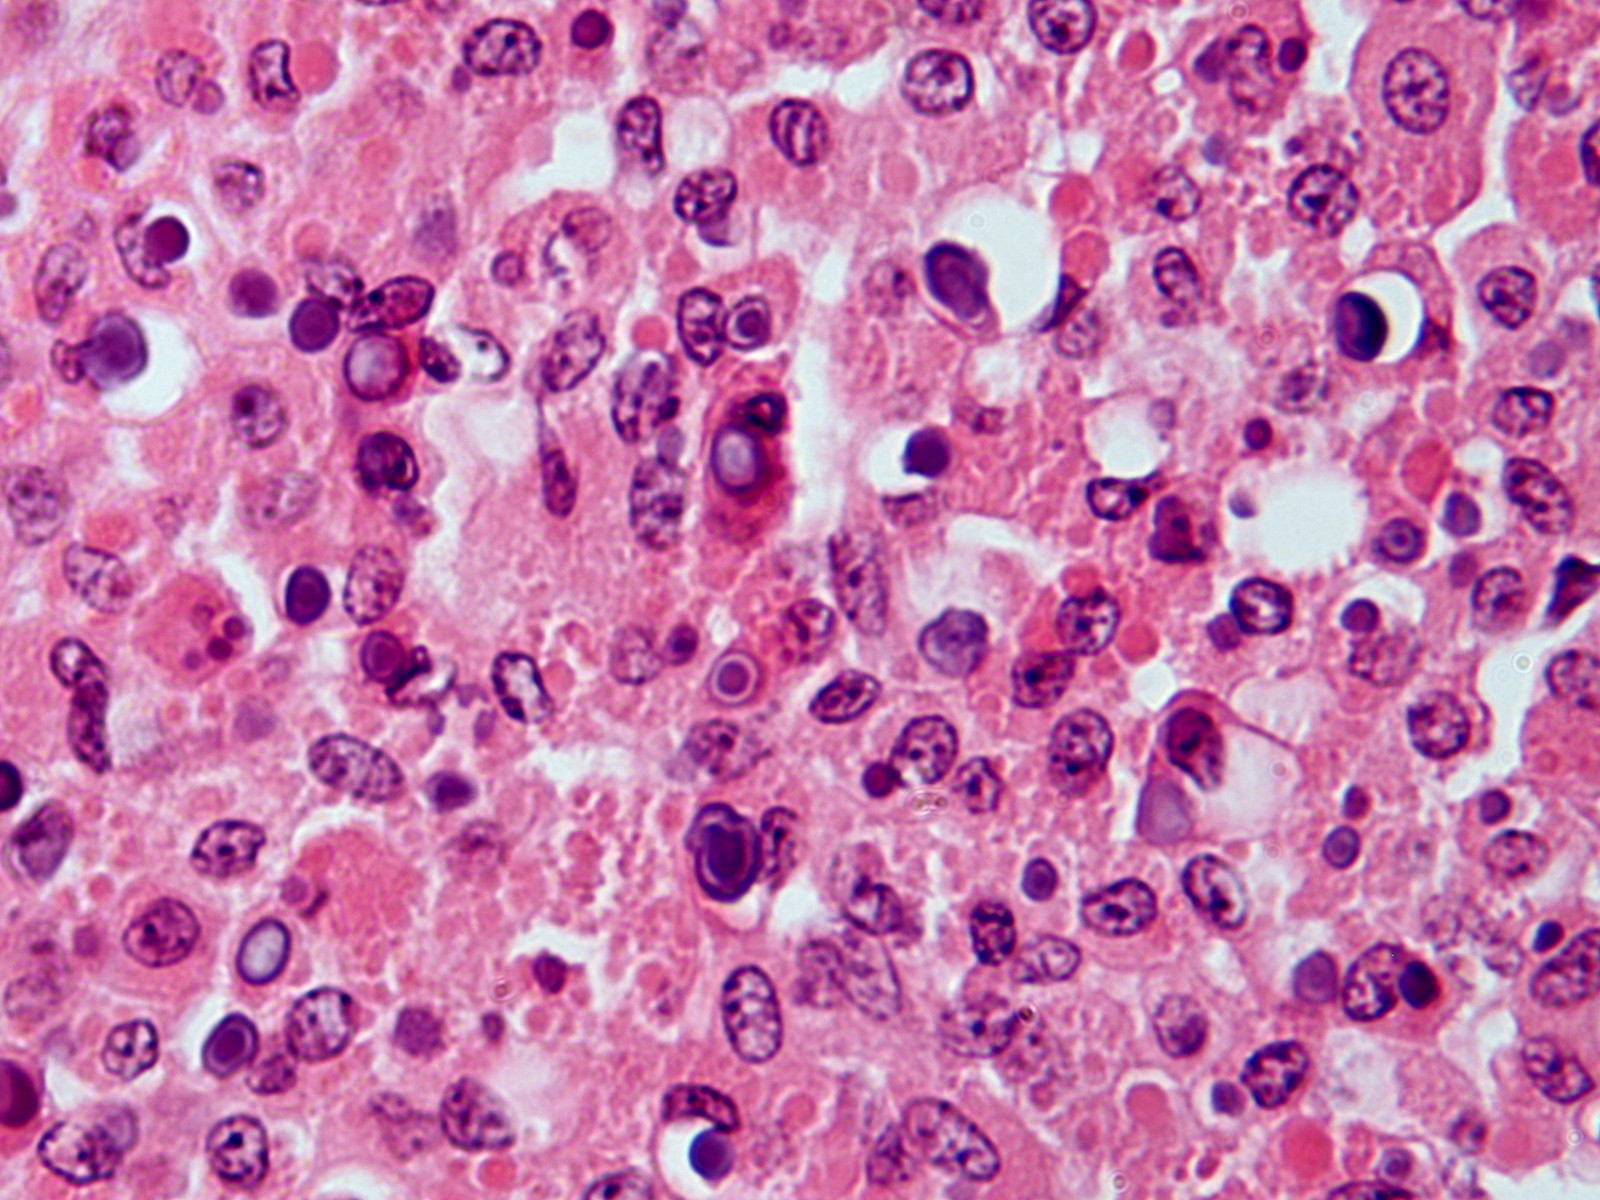

Michaelis-Gutmann bodies bij malakoplakia

Michaelis-Gutmann bodies

Malakoplakie is een zeldzaam beeld bestaande uit gelige of huidkleurige papels of noduli, of een plaque, en soms een ulcus. Het ontstaat bij patiënten met een afweerstoornis (immunosuppressiva, niertransplantatie, lymfoma, AIDS), vooral bij een stoornis in het proces van phagocytose door macrofagen en monocyten. Door een stoornis in de lysomale activiteit zijn de macrofagen niet in staat om bacteriën goed op te ruimen. De gedeeltelijk afgebroken bacteriën hopen zich op in de macrofagen en zijn histologisch te zien in de vorm van calcium en ijzer bevattende basofiele inclusies, genaamd Michaelis-Gutmann bodies. De diagnose wordt vrijwel nooit op het klinisch beeld gesteld, maar blijkt achteraf uit de PA, waarin schuimcellige histiocyten met een eosinofiel cytoplasma te zien zijn, en de Michaelis-Gutmann bodies. Uit de laesies kunnen bacteriën worden gekweekt. De meest geïsoleerde bacterie uit malakoplakie is E. coli, gevolgd door S. aureus, Pseudomonas aeruginosa, en Rhodococcus equi. Malakoplakie wordt meestal gezien op de blaaswand mucosa, de lokatie in de huid is zeer zeldzaam. Cutane voorkeurslokalisaties zijn de perianale en inguinale regio, billen en buikwand. Abcedering en fisteling komt voor.